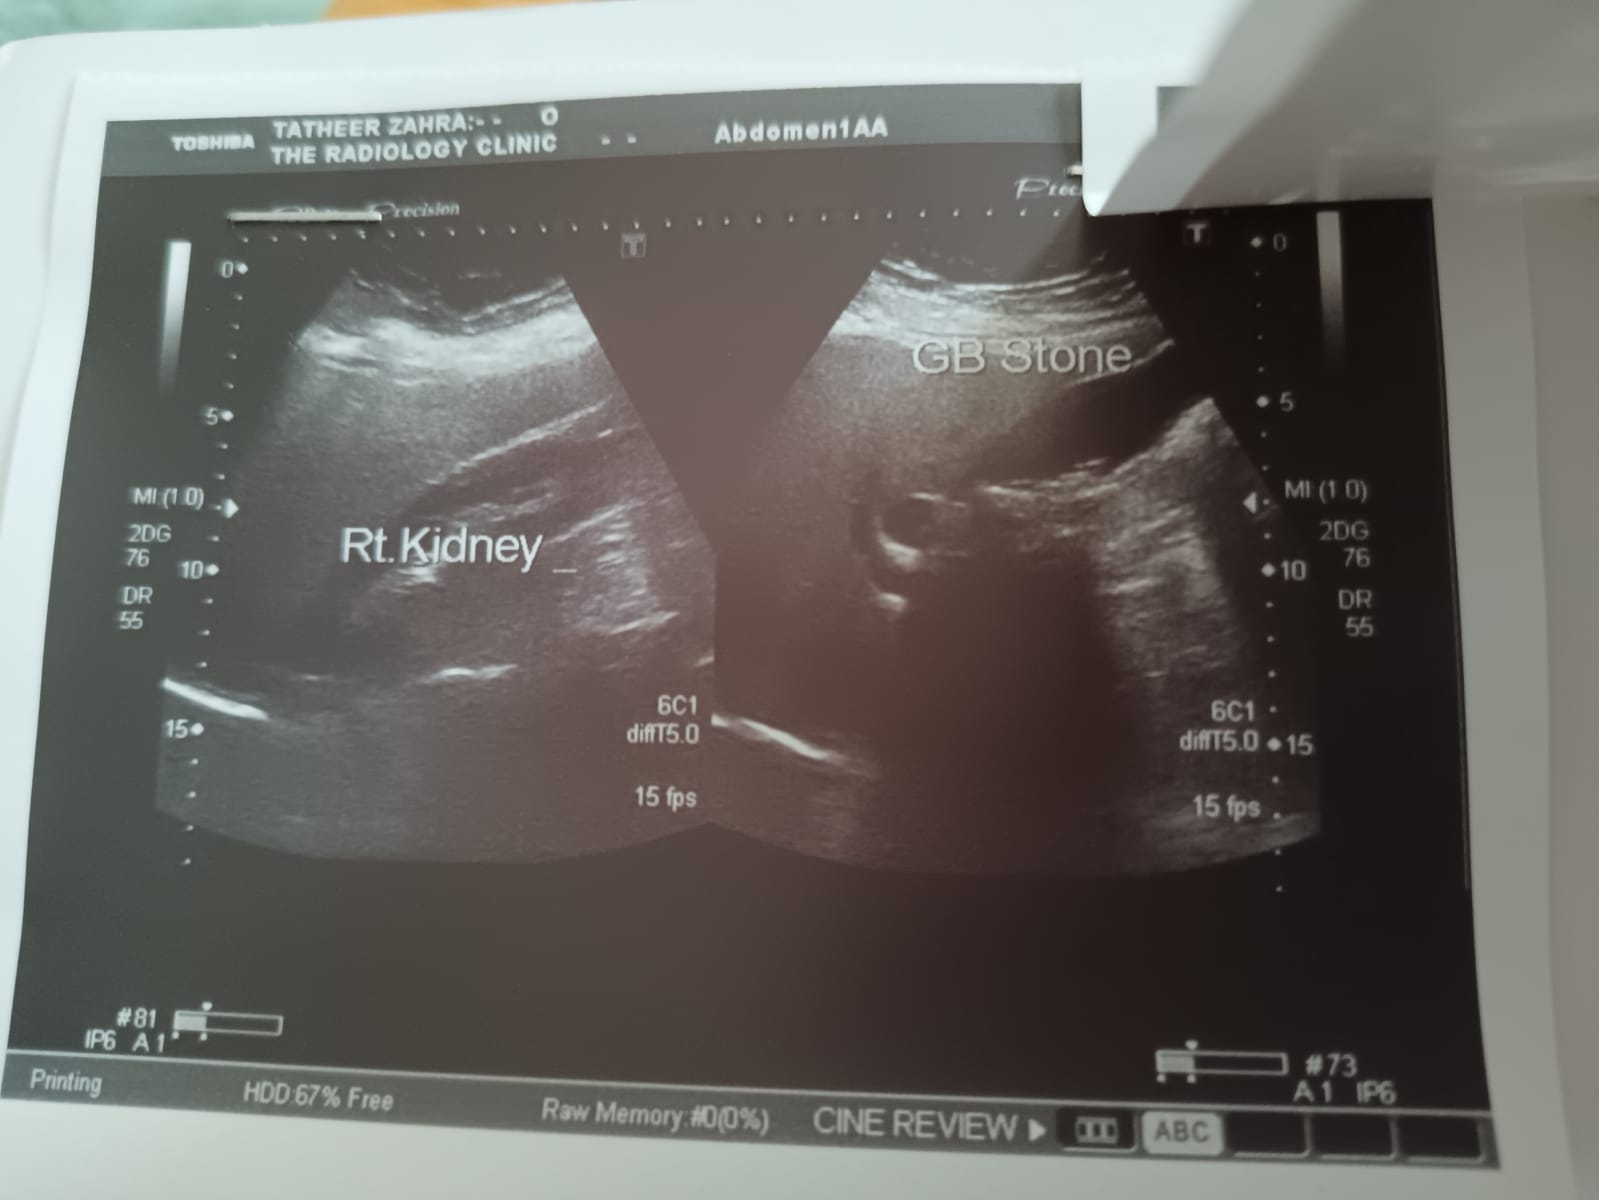

I heard that doing an operation or laser is dangerous for Gallbladder stones in the summer month like June and July because getting sweat after the operation is very dangerous is it true?